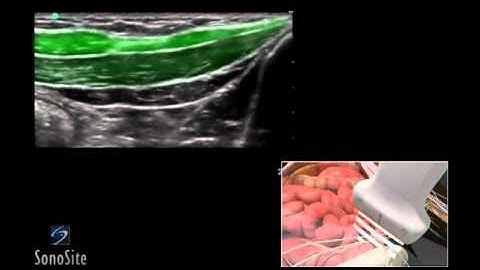

Ultrasound Guided Nerve Blocks